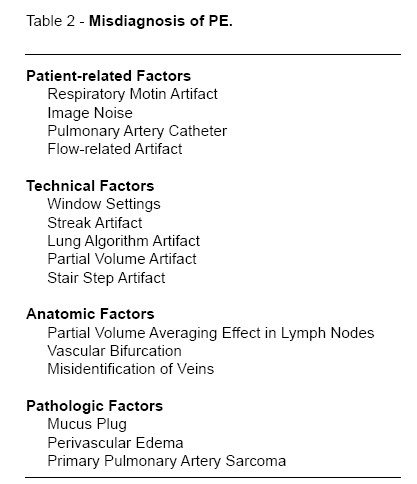

PITFALLS

A table listing potential pitfalls is given (Table 2

) and several cases illustrating them are presented (2,3). Never forget that besides PTE, there are other forms of PE, like gas and tumor embolism (8).